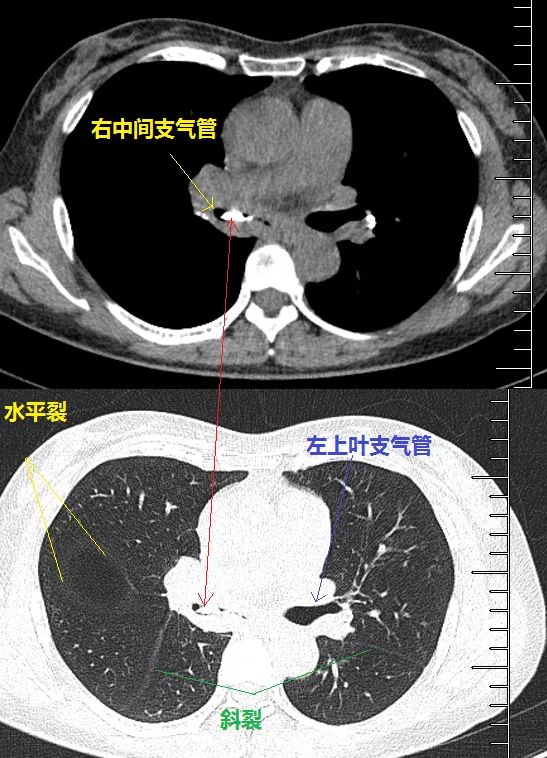

右中間支氣管的鈣化病灶向外移動,鈣化病灶的尖端刺激到支氣管粘膜了(圖16)。

圖16 胸部CT

另外,這個患者的鈣化灶非常危險,因為鈣化灶的一端距離肺動脈才2毫米左右(圖17),支氣管鏡下強行牽拉鈣化病灶很可能會大出血危及生命。

圖17 胸部CT